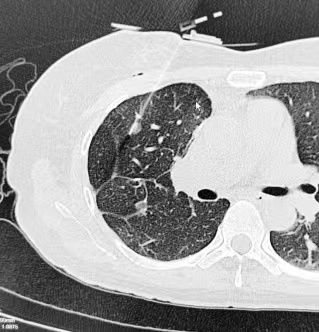

2024年8月11日,手术进行,首先将CT扫描实时数据导入穿刺导航机器人,并在机器人上规划预设好穿刺路径,通过呼吸门控技术过滤掉患者自主呼吸的影响,然后在机械臂红外激光的引导下进行穿刺,穿刺成功后行射频消融治疗。

手术用时半小时。术中采用局部麻醉,患者无明显不适,未出现气胸、血胸等并发症。术后观察,患者无特殊不适,顺利返回病房。术后1天复查胸片无特殊即安排出院。